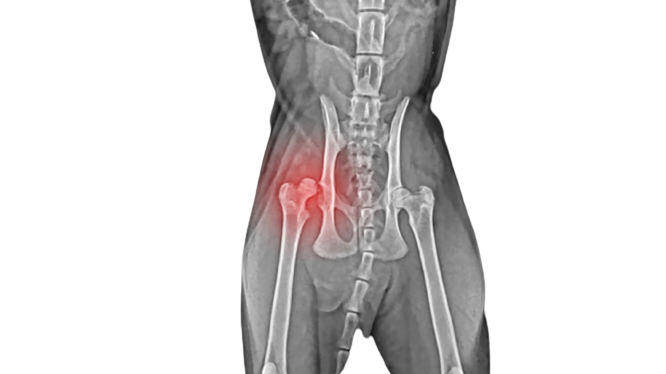

+ ศูนย์การผ่าตัดศัลยกรรมและบริการทันตกรรมสัตว์เลี้ยง กรุงเทพฝั่งธน

ให้บริการศัลยกรรมสัตว์เลี้ยง ทางด้านศัลยกรรมกระดูกและข้อ ศัลยกรรมระบบประสาท ศัลยกรรมโรคตาสัตว์